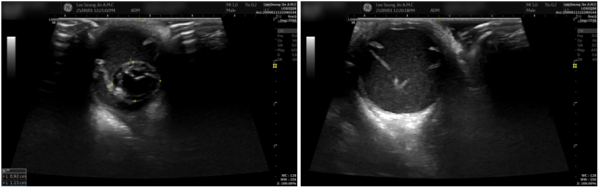

안구 초음파 검사

초음파에서는 수정체가 뒤쪽으로 탈구된 상태가 확인되었습니다.

주변에는 출혈과 염증 산물이 보였고,

이미 망막박리가 진행되어 시력 회복이 어려운 단계였습니다.

안구가 비대해지고 시신경 압박이 심해

상당한 통증이 있었을 것으로 판단되었습니다.